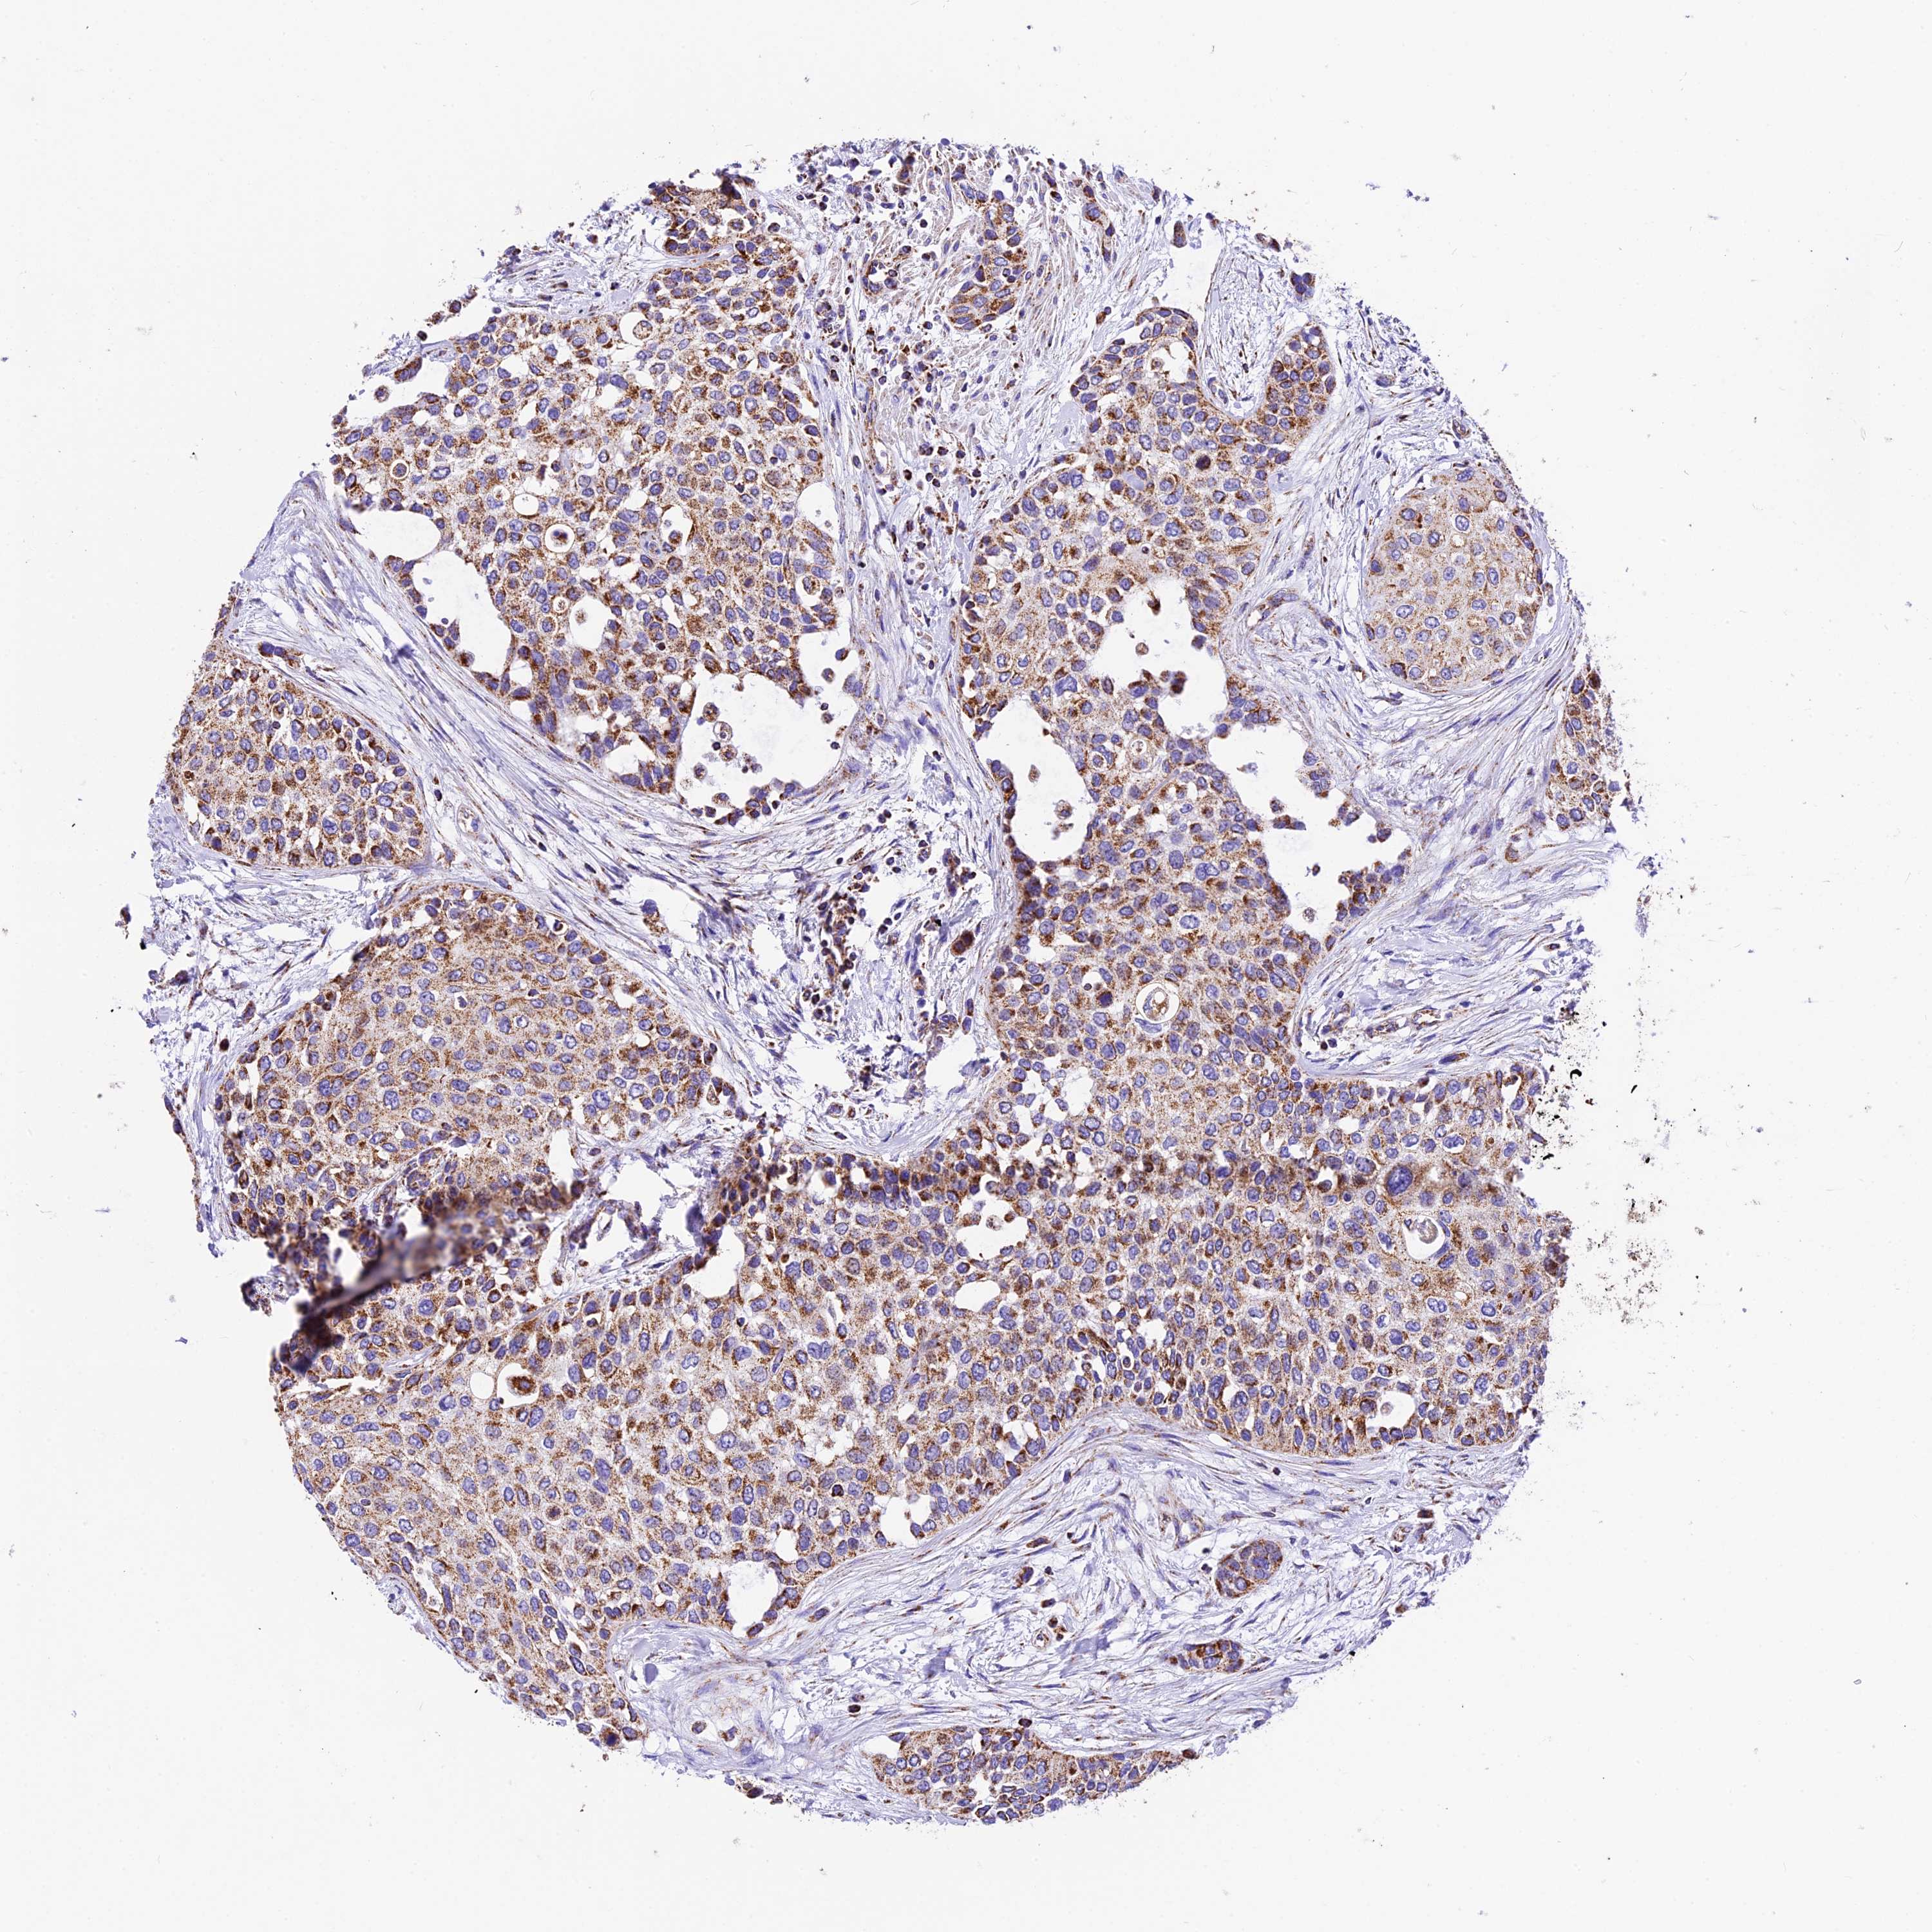

UROTHELIAL CANCER - Protein expressioni

A mouse-over function shows sample information and annotation data. Click on an image to view it in a full screen mode. Samples can be filtered based on level of antibody staining by selecting one or several of the following categories: high, medium, low and not detected. The assay and annotation is described here.

Note that samples used for immunohistochemistry by the Human Protein Atlas do not correspond to samples in the TCGA dataset.

Antibody stainingi

Antibody staining in the annotated cell types in the current human tissue is reported as not detected, low, medium, or high, based on conventional immunohistochemistry profiling in selected tissues. This score is based on the combination of the staining intensity and fraction of stained cells.

Each image is clickable and will lead to virtual microscopy that enables deeper exploration of all samples and also displays staining intensity scores, fraction scores and subcellular localization as well as patient and tissue information for each sample.

Antibody HPA041575

Antibody HPA048098

Staining

High

Medium

Low

Not detected

Intensity

Strong

Moderate

Weak

Negative

Quantity

>75%

75%-25%

<25%

None

Location

Nuclear

Cytoplasmic/membranous

Cytoplasmic/membranous,nuclear

Urothelial carcinoma, High grade

Urothelial carcinoma, Low grade

Urothelial carcinoma, NOS